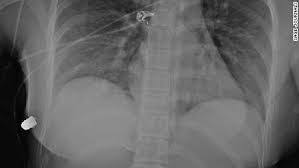

Woman S Breast Implant Deflects Bullet Saving Her Life Cnn

Woman S Breast Implant Deflects Bullet Saving Her Life Cnn from cdn.cnn.com